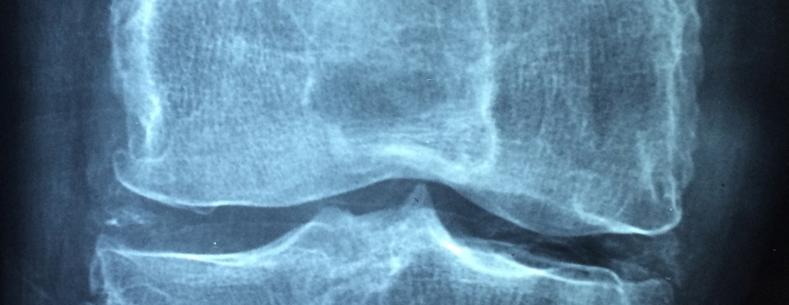

There are many different types of arthritis and chronic MSK conditions, including osteoarthritis, inflammatory arthritis, connective tissue diseases, back pain, bone disease (such as osteoporosis), soft tissue rheumatism, and chronic musculoskeletal pain. Osteoarthritis is the most common form of arthritis. Often thought of as ‘wear and tear’ of the joints, it affects people as they get older but is also common amongst people of working age. Treatment includes pain medication, lifestyle measures (e.g. weight management and exercise), and in severe cases joint replacement surgery. The Chartered Society of Physiotherapy reports that almost half a million people are living with osteoarthritis in Wales.